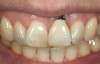

Fig 3. A patient presented with a high smile line and midfacial recession of the maxillary right lateral incisor as evidenced by the increased tooth length compared with the contralateral lateral incisor.

Fig 4. Intraoral view of tooth No. 7 with the gingival zenith more apical than the adjacent central incisor and canine tooth.

Problem: The implant is placed too facially, and there is significant labial gingival recession, contour change, and mucosal discoloration around the implant, abutment, and crown (Figure 3 and Figure 4). The implant attachment apparatus is intact and healthy, but the patient has a thin periodontal phenotype.

The following case report provides an example of this case scenario: A 28-year-old white female patient presented with her maxillary right lateral incisor significantly longer than the contralateral tooth following restoration of an existing crown that was 10 years old (Figure 3). The patient was dissatisfied with the esthetic appearance of the restoration due to the increased length, recession of the gingival tissues, and discoloration of the surrounding mucosa (Figure 4). Similar to case scenario No. 1, the first step in treatment was to decoronate the healthy implant by placing a flat surgical cover screw and employing a provisional resin-bonded-retained (RBR) prosthesis as a transitional fixed restoration (Figure 5 and Figure 6). The gingival augmentation in situ was allowed to take place for 2 to 3 weeks and was evaluated after that time (Figure 7).